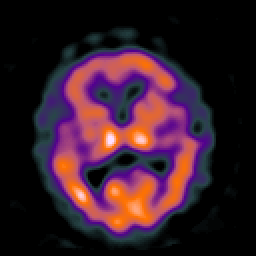

Huntington's Chorea, MR -- Slice #10

[Home][Help][Clinical] Slice 10